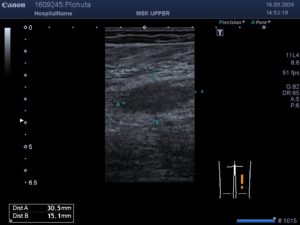

УЗД нервів при травмах